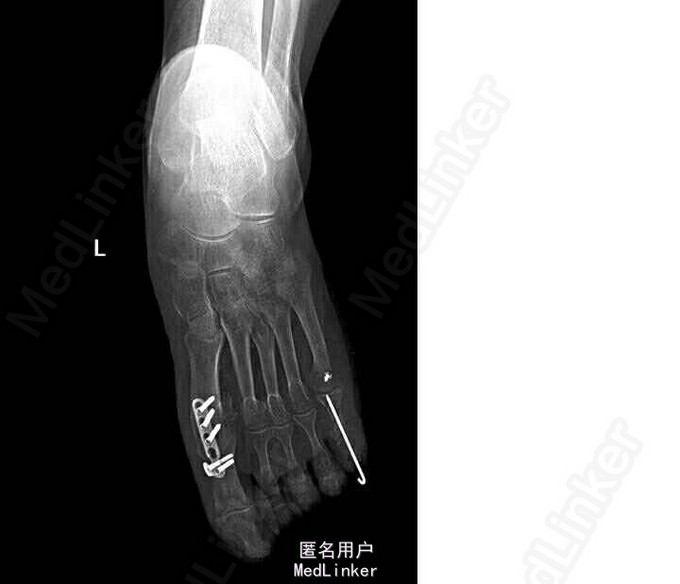

诊断:双侧扁平足(左侧重),左足截骨矫形术后,左足第一、五跖趾骨关节炎 局麻下行“左足矫形术(第五趾间关节融合内固定,第一、三、五趾骨屈肌腱松解,第一趾骨伸肌腱紧缩术)”。

术后行走疼痛明显改善,规律复查